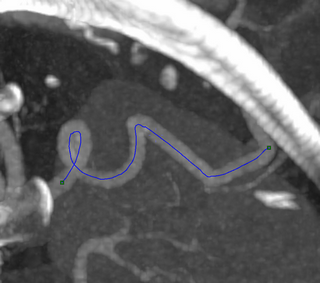

Path found through a curved vessel

The XStream® HDVR® SDK supports a feature to automatically compute and generate a path along a vessel or other navigable channel, such as a nerve channel trace, or other path through a channel in the dataset. The path-finding feature specifies start and end points, and other path-finding operation parameters. The path-finding algorithm then sends out tracers from the start and end points that travel through the channel. If the tracers from the start and end points get within a threshold distance of each other, they will connect and a path will be established. The threshold distance and other parameters for the path-finding operation can be customized, based on the size and material type of the channel through which a path is being found.